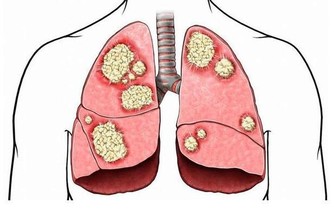

丙肝也是一種常見的病毒性肝炎,是導致肝硬化、肝癌的主要原因之一,但是它的篩查率和治療率遠低於乙肝。

丙肝和其他病毒性肝炎不同,它不容易被人體的免疫系統識別,這樣就很容易潛伏在人體內,病毒就會慢慢地損害肝細胞,從而危害人體。沒有得到及時治療的丙肝患者,就會逐漸發展成肝硬化,甚至是肝癌。